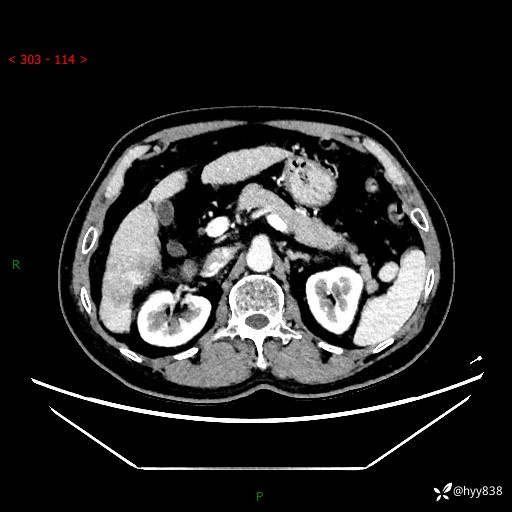

肝脏CT平扫